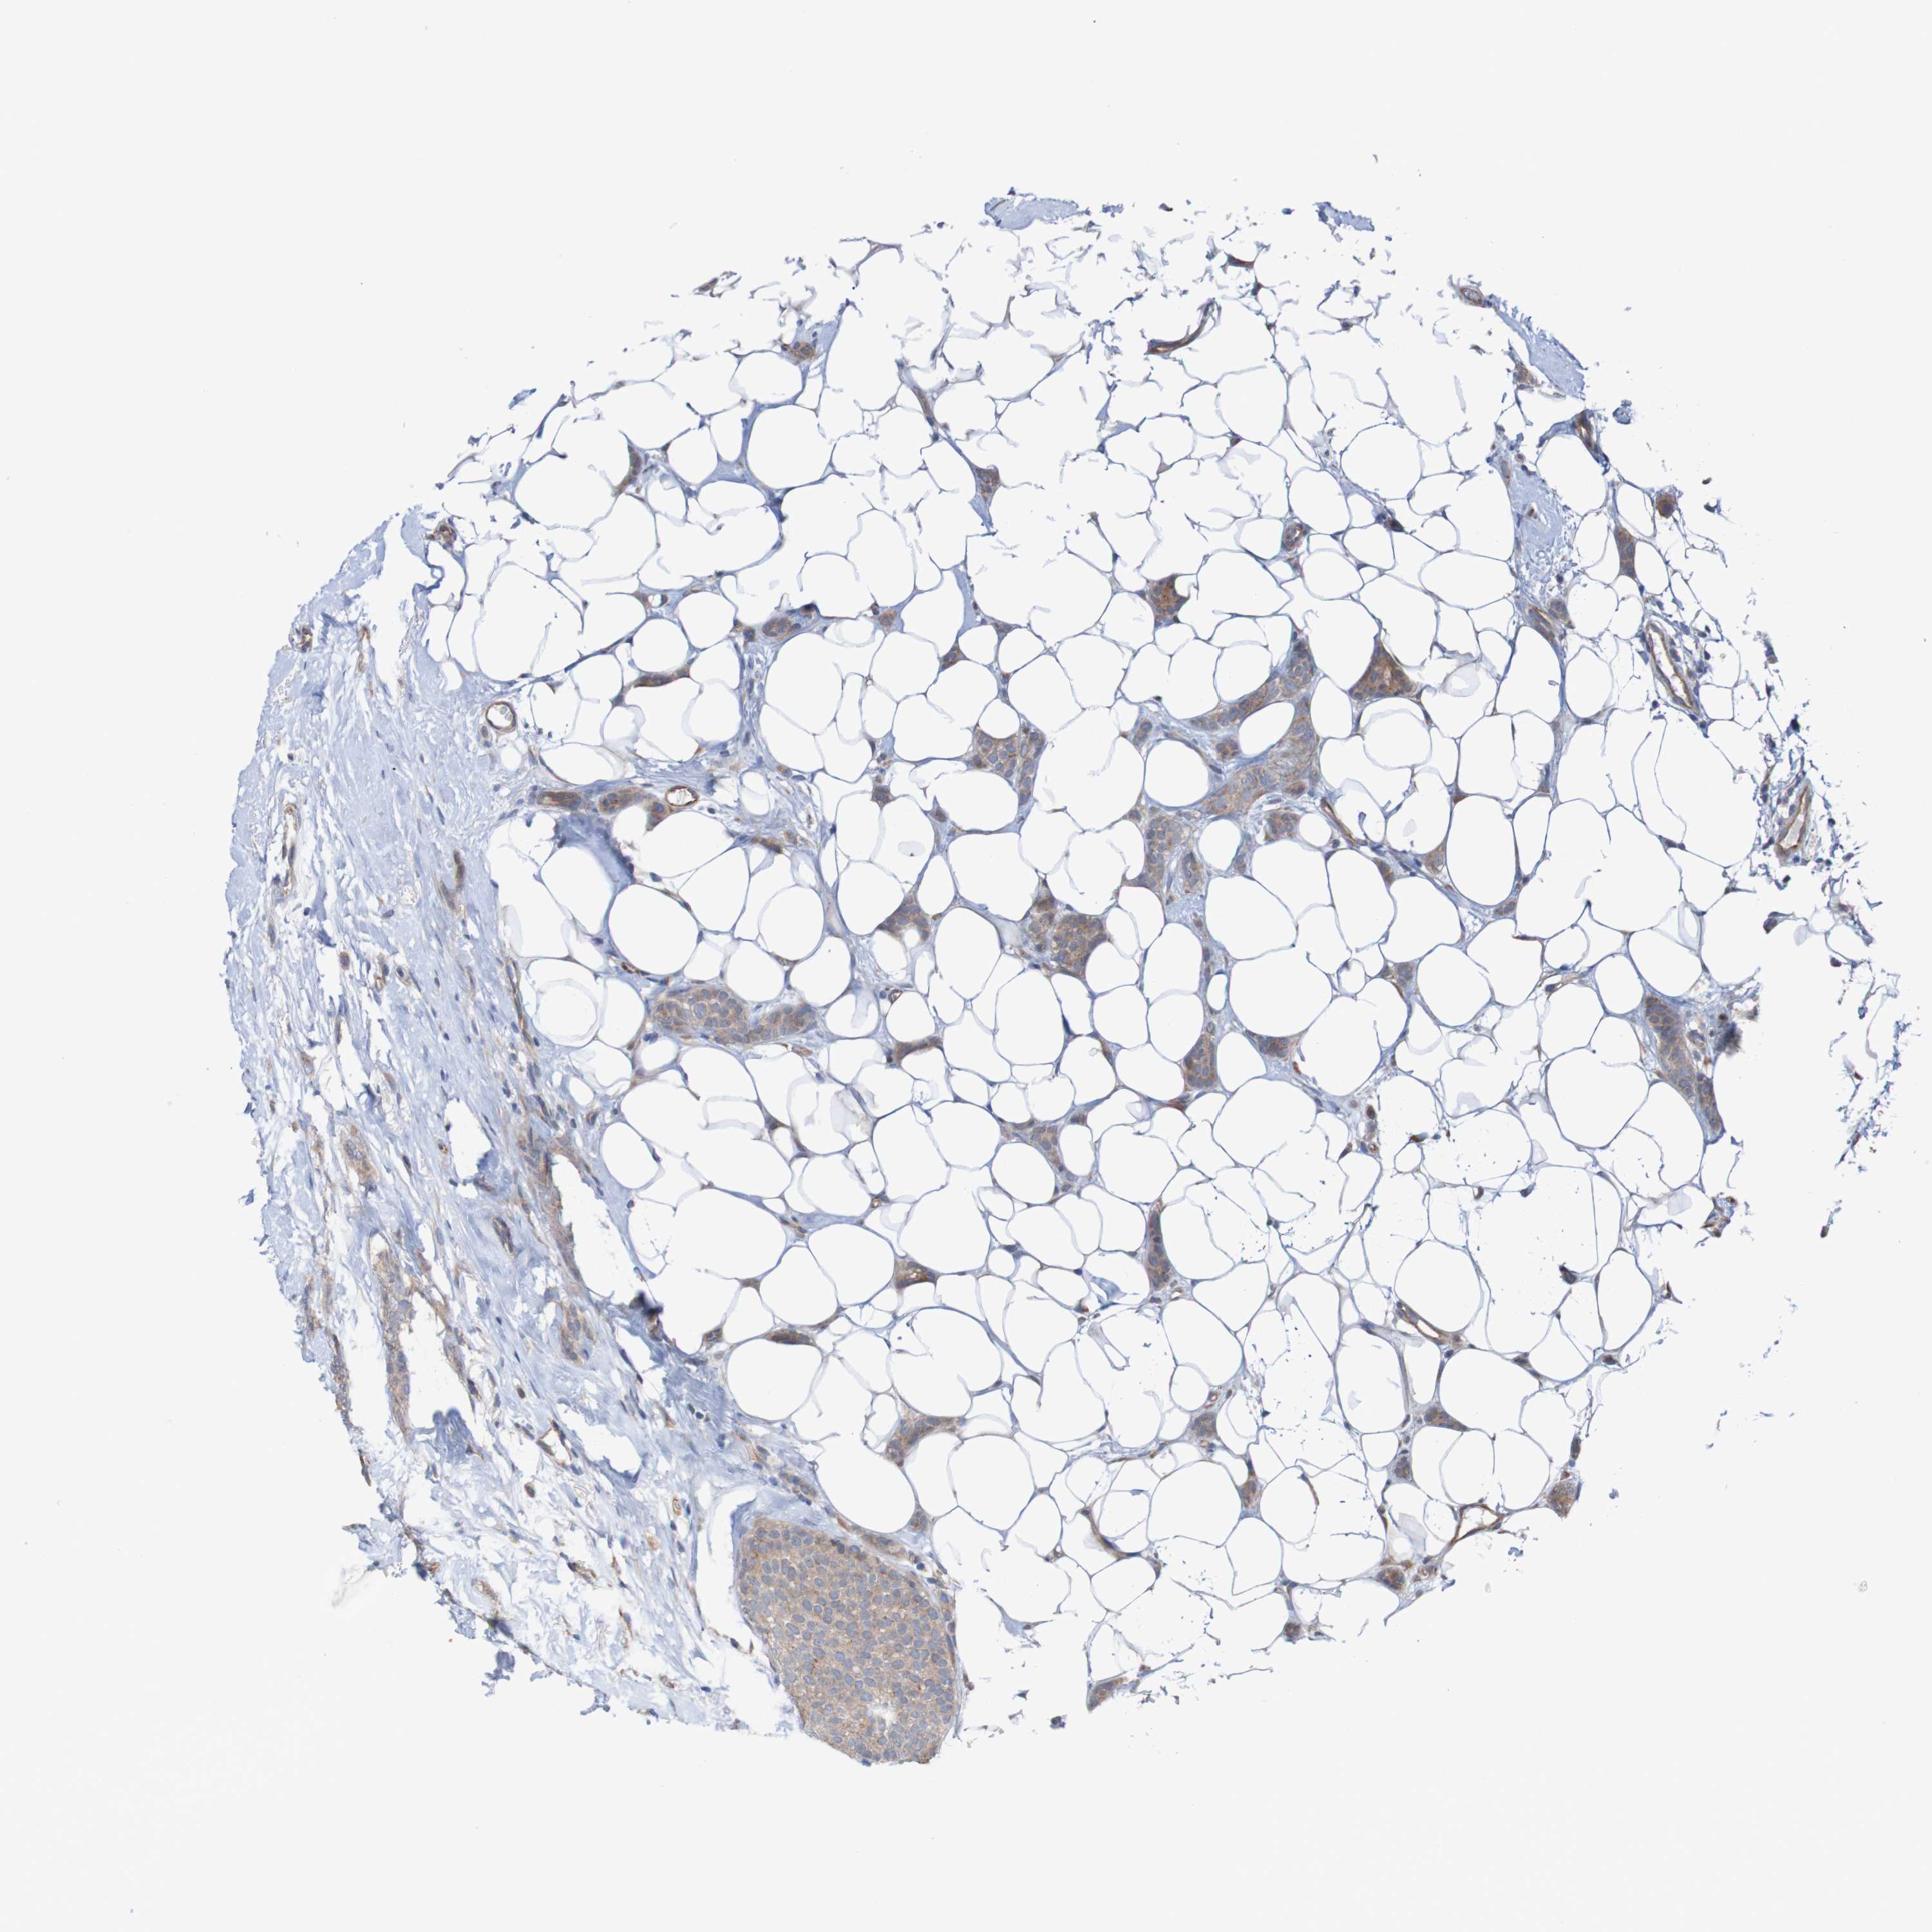

CANCER BREAST CANCER Show tissue menu

BRCA TCGA BRCA VALIDATION PROTEIN EXPRESSION